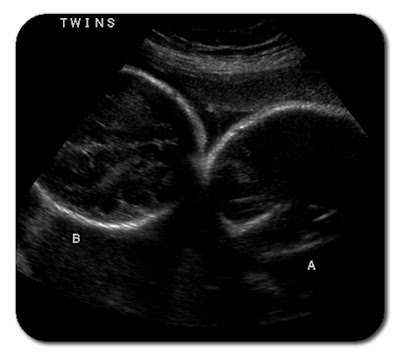

This is a picture of both of their heads together. You'd think they'd have more room if one was turned the other way, but oh well.